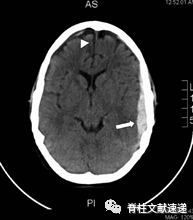

图注:40岁女性,既往多次腰椎手术史,再行翻修手术中发现发现硬膜缺损并给予修复。术后三周,病人出现进行性头痛。腰椎磁共振成像显示术区积液。再次手术探查,但未见渗漏。患者头痛持续,术后24小时进行CT扫描,显示右侧硬脑膜下血肿(SDH),中线移位。病人接受紧急颅骨切开引流减压。随访CT显示SDH恢复良好。